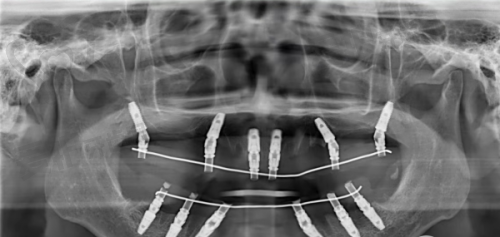

首先,患者需要到兰州诺贝尔口腔进行全方面的口腔检查,包括口腔X光片、CT扫描等,以确定牙槽骨的情况和是否适合种植。然后,简波简院长会根据检查结果制定个性化的种植方案。在种植手术中,医生会在局部麻醉下将人工牙根植入牙槽骨内。这个过程一般不会有明显的疼痛感。术后,患者需要遵循医生的嘱咐进行护理,等待人工牙根与牙槽骨结合。通常需要几个月的时间,待结合牢固后,再安装牙冠,整个种植过程就完成了。